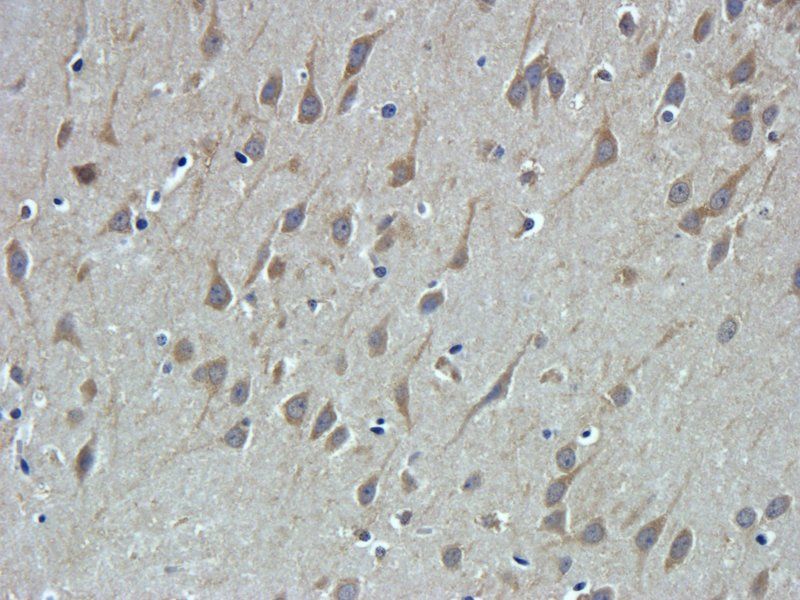

Immunofluorescence analysis of HepG2 cells using TRPV1 antibody